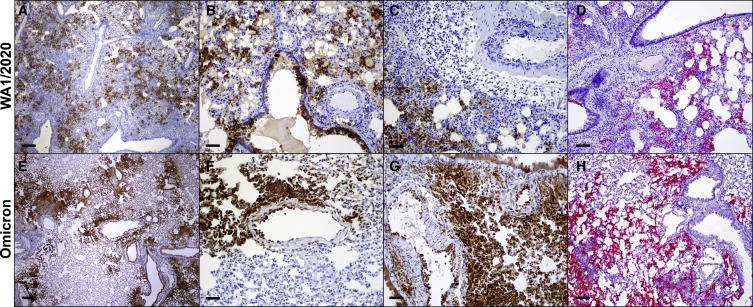

图 4. SARS-CoV-2 Omicron 变异体在肺中的分布

(A–H)感染SARS-CoV2 WA1/2020(A–D)和Omicron(E–H)的仓鼠中核衣壳蛋白(棕色)的免疫组织化学和病毒RNA(红色)的RNAscope原位杂交。

Omicron 感染后肺部病理减少:在感染后第4天,与WA1/2020感染的仓鼠相比,Omicron感染的仓鼠表现出细支气管上皮变化、间质炎症和实变以及内皮炎的减少,与剂量为5×104 PFU的WA1/2020感染的动物相比,剂量为2.5×105 PFU的Omicron感染的动物的肺部病理学评分较低。尽管整体病理学显著降低,但与WA1/2020感染的仓鼠相比,Omicron感染的仓鼠肺中SARS核衣壳(SARS-N)阳性细胞的数量与WA1/2020感染的仓鼠相似,但显示出每单位肺面积Iba-1阳性细胞(巨噬细胞)和髓过氧化物酶阳性细胞(中性粒细胞)减少的趋势。WA1/2020和Omicron感染的动物都有SARS-N阳性的细支气管上皮和肺细胞。Omicron感染的动物的鼻甲病变明显,但与WA1/2020感染的仓鼠相比,其分布、严重程度或病毒阳性率没有差异。